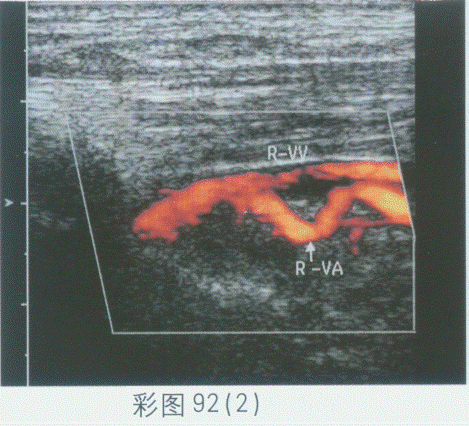

229、单项选择题

临床资料:女,74岁,主诉转颈后眩晕。超声综合描述:左侧椎动脉内径0.33cm,走行正常,右侧椎动脉内径0.32cm,走行纡曲,入椎前呈"M"形,椎间段节段性走行纡曲,CDFI:纡曲段血流充盈良好。见彩图92。

超声提示()。

A.双侧椎动脉正常声像图

B.双侧椎动脉不对称

C.右侧椎动脉闭塞

D.右侧椎动脉走行纡曲(椎前段、椎间段)

230、单项选择题 超声检查半月板最理想的探头频率是()。